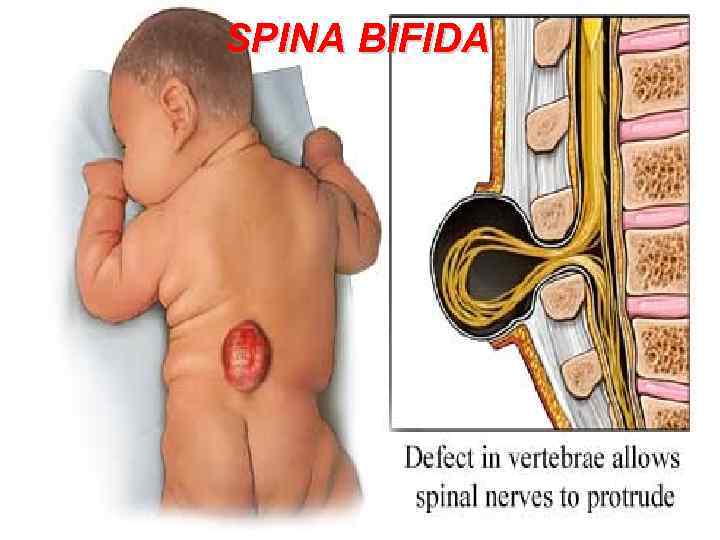

SPINA BIFIDA 111